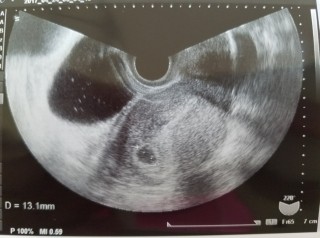

3回の人工授精と2回の体外受精を経て妊娠しました。前回は、化学流産で胎嚢確認できなかったので、胎嚢と卵黄嚢が見れて嬉しいです。大きさは13.3mmでした。

このまま、順調に成長してくれることを願って2週間後の心拍確認に臨みます!!